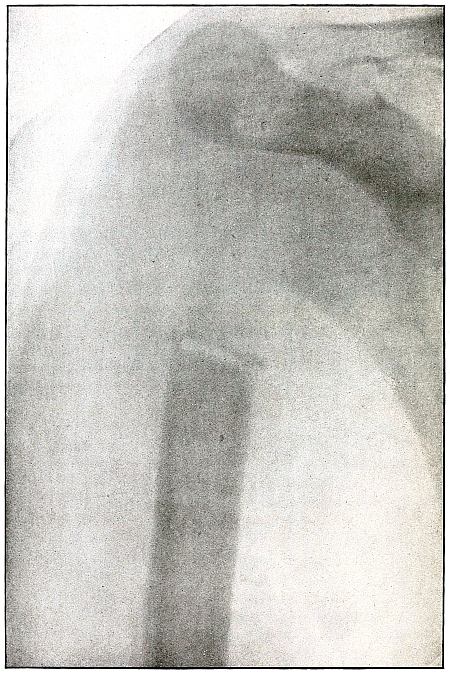

Rifle—Plate 8.

UPPER EXTREMITY.

Compound Fracture of the Humerus in Advanced State of Repair with Callus Formation.

Wound of entrance, just above middle of anterior aspect of arm.

Wound of exit, about the same height, posteriorly.

The course of the missile was anteroposterior, with high velocity of short range through the bone with a splitting effect, leaving a few fragments, large and small, which were not much displaced and caused but little deformity.

Wound was not infected. The absorption of smaller and the overlapping of larger fragments caused some shortening.

Treatment, expectant.

Results, favorable. [Pg 28]